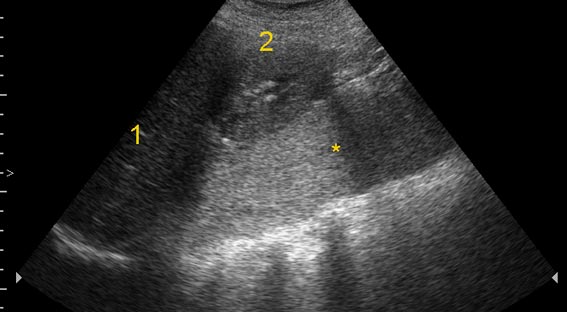

УЗИ, гнойный псоит

Женщина, 45 лет. Боли в правой подвздошной области, правом бедре, невозможность поднять прямую правую ногу.

Абсцесс задренирован, отмыт, больная выписана с выздоровлением.